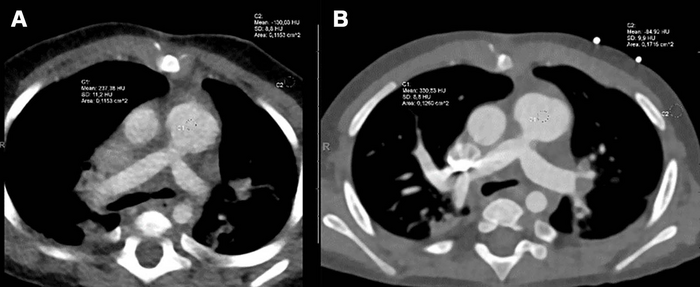

Axial contrast-enhanced dual-source CT (DSCT) and photon-counting CT (PCCT) images for comparison of image quality in the same infant who for clinical reasons underwent both (A) DSCT at 308 days old and (B) PCCT 14 days later at 322 days old. The male infant had a complete ventricular septum defect, Rastelli type A, postoperative situs after stenosis of the left and right lung veins and a so-called sutureless repair, banding of the pulmonary artery, and duct ligation. CT was performed again for clinical reasons (sonographic suspicion of pulmonary venous restenosis). On a five-point scale, the diagnostic image quality score of DSCT (A) was rated as moderate (score of 3), whereas that of PCCT (B) was rated as excellent (score of 5).